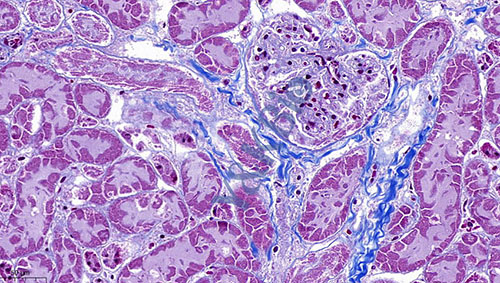

重庆Masson染色是病理染色服务中比较常见的一种,Masson染色用于胶原纤维和肌纤维的染色及鉴定;染色结果:胶原纤维呈蓝色、肌纤维呈红色、细胞核呈蓝黑色。